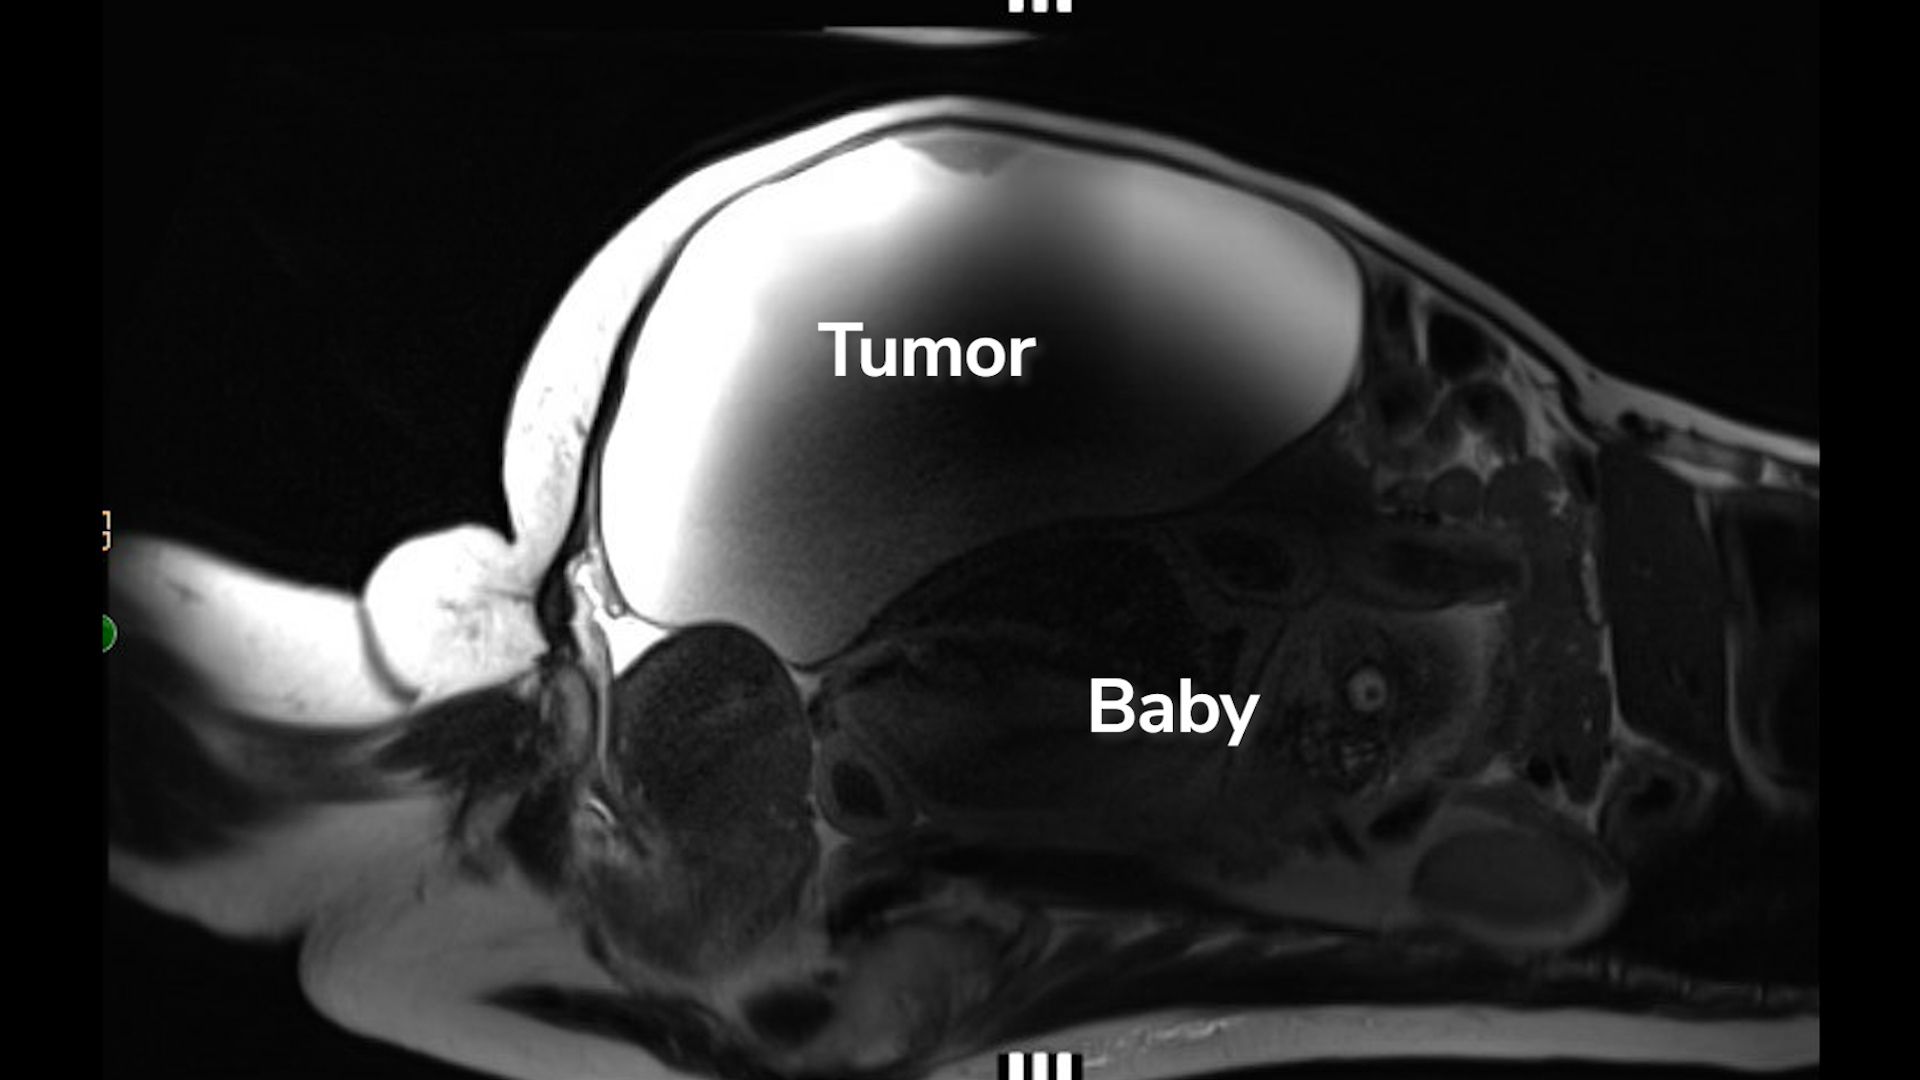

Que s’est-il passé ensuite : Une échographie pelvienne et une IRM ont révélé que même si la jeune fille avait un utérus, il lui manquait à la fois un col et un vagin. Les médecins ont ensuite confirmé leurs découvertes par une laparoscopie, une procédure au cours de laquelle un tube équipé d’une caméra est guidé dans le corps à travers une incision en trou de serrure. Ils n’ont vu ni col ni vagin, mais ils ont vu des ovaires et des trompes de Fallope sains, sans aucune preuve de endométriose.

L’équipe médicale a ensuite exploré diverses options chirurgicales de traitement, notamment l’ablation de l’utérus. Après avoir discuté avec la jeune fille et sa famille, les médecins ont opté pour une intervention chirurgicale visant à préserver la fertilité, en procédant à une vaginoplastie. Au cours de la procédure, ils ont créé un vagin avec une ouverture cervicale où il se connectait à l’utérus.

Des années plus tard, en 2010, à l’âge de 28 ans, elle a arrêté de prendre des moyens contraceptifs parce qu’elle et son partenaire voulaient commencer à essayer d’avoir un enfant. Après avoir tenté de concevoir pendant un an, le couple a fait appel à des spécialistes de la fertilité. Un test hormonal a indiqué que son nombre d’ovules était inférieur à la moyenne pour son âge. Une IRM pelvienne a également révélé une petite accumulation de sang menstruel dans l’utérus, suggérant que du tissu cicatriciel pourrait obstruer la partie supérieure du vagin.